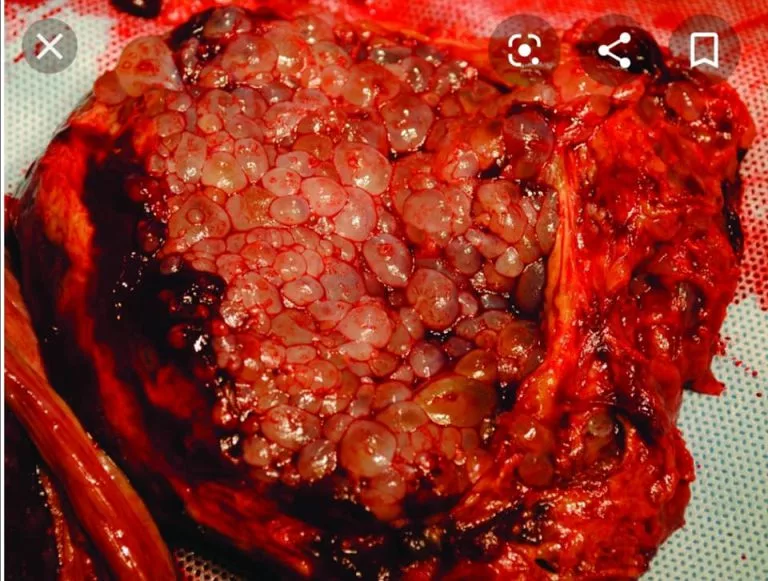

Kehamilan anggur merupakan satu jenis kehamilan yang tidak berkembang menjadi janin sempurna. Akibat masalah semasa persenyawaan, tisu embrio dan plasenta tidak berkembang dengan normal, sebaliknya menjadi gugusan tisu berbentuk gelembung atau sista yang menyerupai buah anggur.

Dalam perubatan, ia dikenali sebagai Hydatidiform mole dan diklasifikasikan kepada dua jenis: lengkap (complete mole) dan separa (partial mole).

Kehamilan anggur lengkap: berlaku apabila ovum kosong disenyawakan oleh satu atau dua sperma. Tisu persenyawaan ini mengandungi 46 kromosom, tetapi semuanya daripada bapa sahaja. Tiada janin terbentuk, hanya gugusan tisu seperti anggur.

Di bawah mikroskop, gugusan tisu ini terdiri daripada struktur tisu plasenta (villi) yang membengkak dan kumpulan sel plasenta (trophoblasts) yang bercambah. Seluruh tisu plasenta harus dikeluarkan, dan ibu perlu menjalani pemeriksaan berkala sehingga penyakit ini benar-benar tiada.